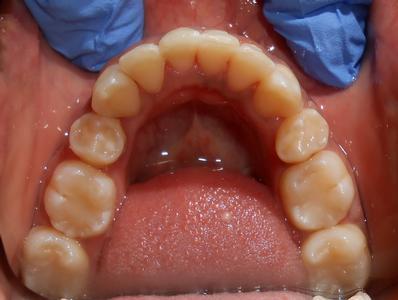

Dental Braces Smile Transformation: Patient Case Study